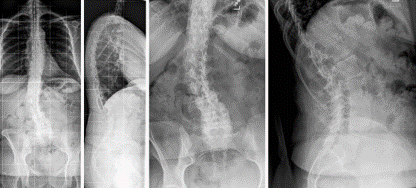

图5 脊柱远端融合节段越多,如包括L5-S1水平固定到骶骨或髂骨,发生交界性后凸的可能性越大

图6 长节段融合固定上固定椎(UIV)选择在胸10-12胸腰椎交界区是PJK的风险因素之一